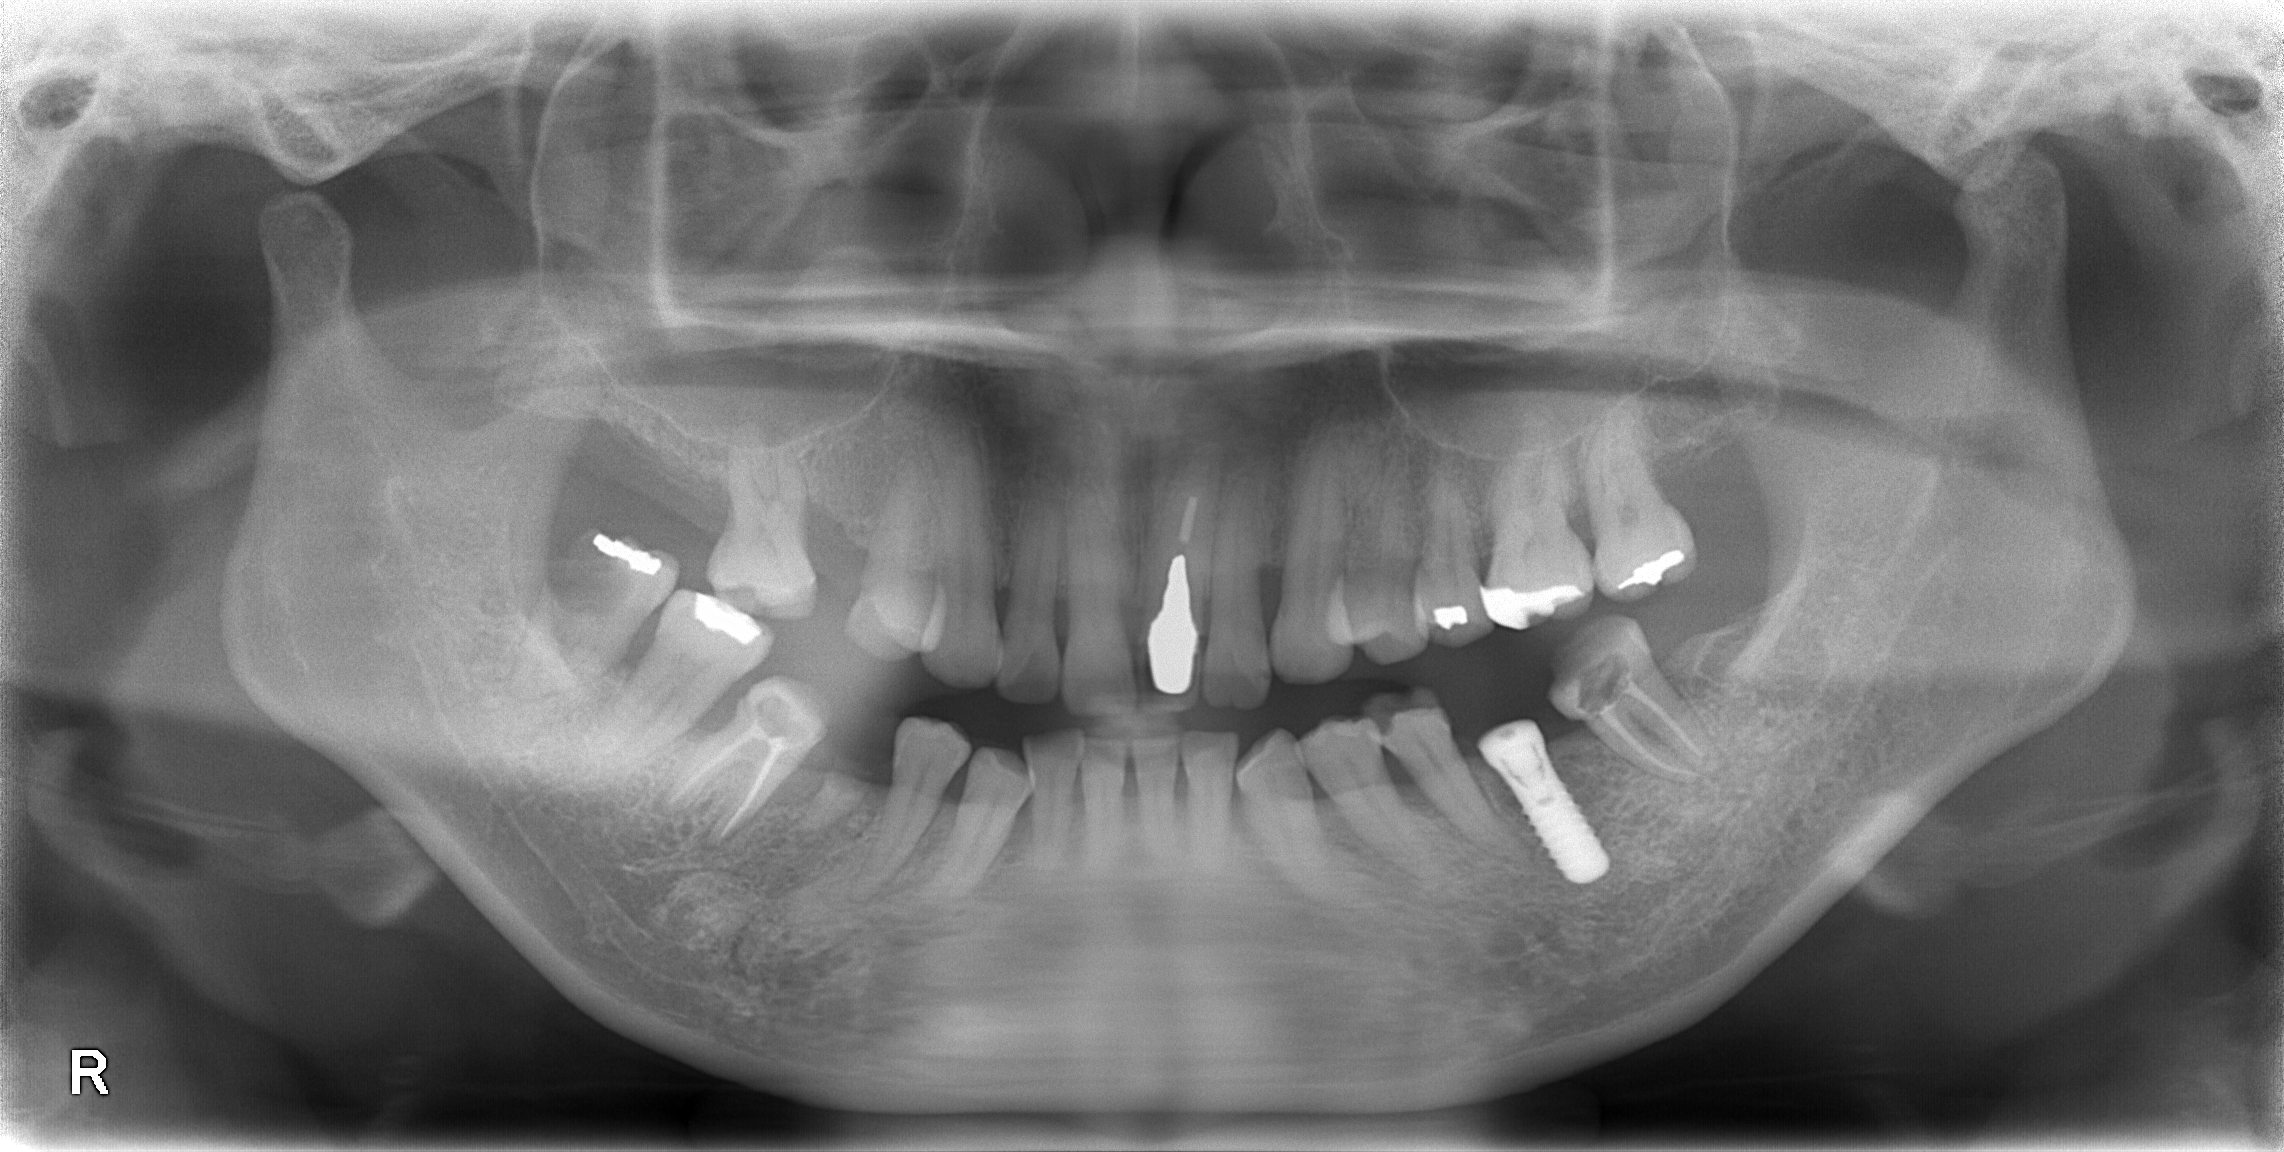

重度虫歯からのインプラント・入れ歯治療(*^-^*)